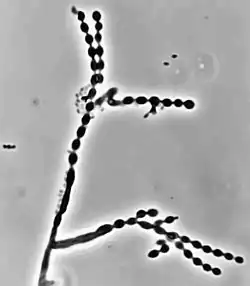

Cladophialophora carrionii is part of a group of melanized fungi, also known as "black yeasts" because its mycelial form has a dark green colour and its conidia have brown pigment.[2][6] Colonies grow at a modest rate on Sabouraud dextrose agar.[1] The conidia of C. carrionii are unicellular oval-shaped spores that are distinguishable due to the presence of two lightly pigmented scars.[6][7] Conidia vary in length (1.5-3.0 × 2.0-7.5 μm).[1] Its long conidiophores are similar to the genus Cladosporium, which comes from the Latin word "clado", meaning branched.[1] The genus Cladophialophora is distinguished from Cladosporium because in addition to chains of conidia, members of the genus Cladophialophora also produce phialides.[8] Cladophialophora carrionii is a dimorphic pathogen that changes states from a mycelial form to a muriform, yeast-like state once it invades its host.[3] Muriform cells are golden-brown in colour due to melanin deposition and have thick cell walls.[2][3]

Like many other black yeasts, C. carrionii is sensitive to temperatures above 37 °C.[6] It can be distinguished in culture by the presence of its urease enzyme hydrolyzing urea[9] and its inability to liquefy gelatin.[7][10] Altering temperatures or micronutrient levels such as calcium and phosphate affects whether C. carrionii is in the mycelial or muriform state.[2] The fungus transforms to muriform cells under conditions of temperature between 25 °C to 37 °C, 0.1 mM Ca2+, and a pH of 2.5.[8] It produces multiple conidia in long, straight chains that bud off the hyphae, with the youngest conidia farthest from the hyphae.[2] There is no sexual state known for C. carrionii.[6]